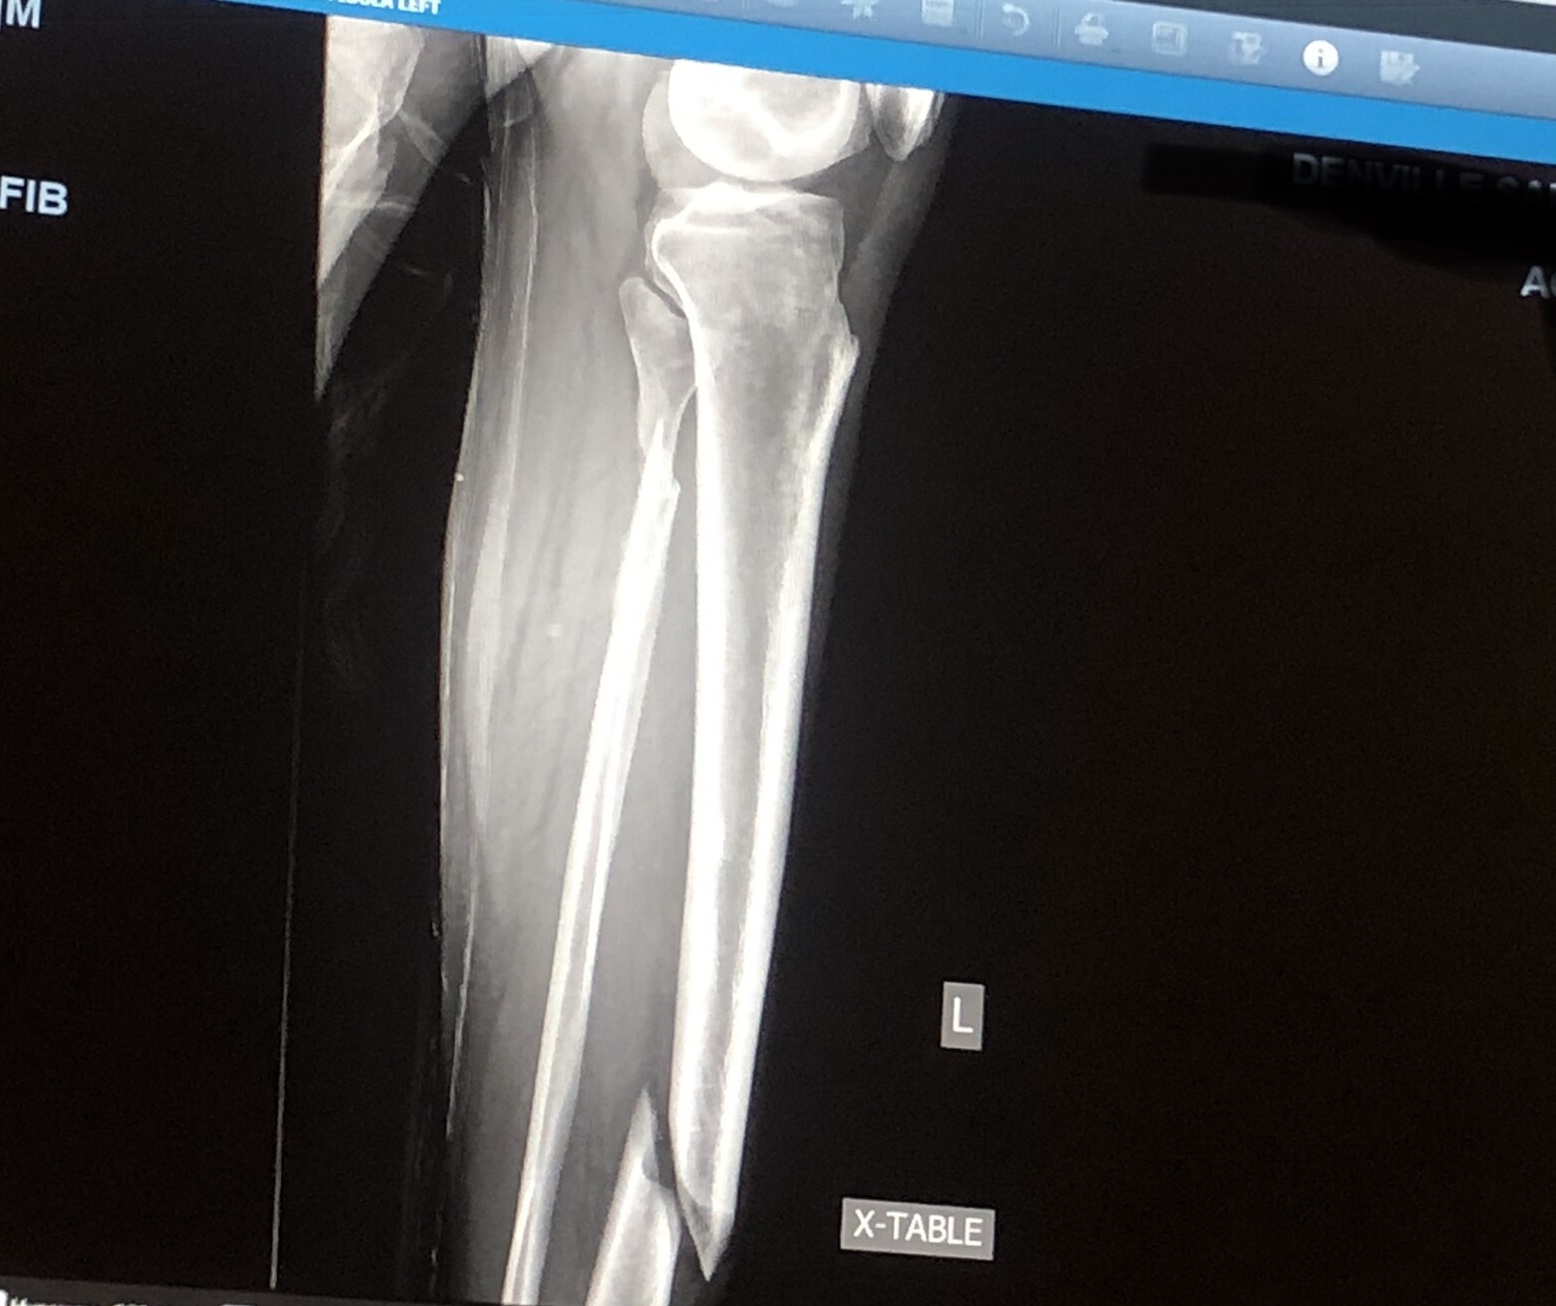

BD96A629-6895-4030-9F59-33B01281356D.jpeg Up until age 54 I had never broken a bone, never had an operation of any kind - fuck I never even had stitches. I think I sprained my pinky finger once. That’s it. And I didn’t exactly lead a sheltered life. I spent entire days walking in the woods, along railroad tracks and climbing into old iron mines. Tackle football, jumping my bike over shit, then later in life a series of drunken shenanigans.

Then early one morning I was laid low by black ice in my own damn driveway. Broken tibia and fibula and a couple of cracked ankle bones. I had a rod inserted in the tibia, screws, etc. I checked off the broken bone, operation and stitches boxes all in one fell swoop.

December 2020. 3 days before Christmas.

The orthopedist did a hell of a job. Other than some knee soreness - that’s the point where they slide the rod down into the tibia- my leg and ankle feel great.

Yep my house, on a hill, moving our cars around when I stepped on black ice. My right foot slid, my left stayed planted. Everything after that happened in slow motion. I felt and heard the snap and had time to think “this is going to be bad”.